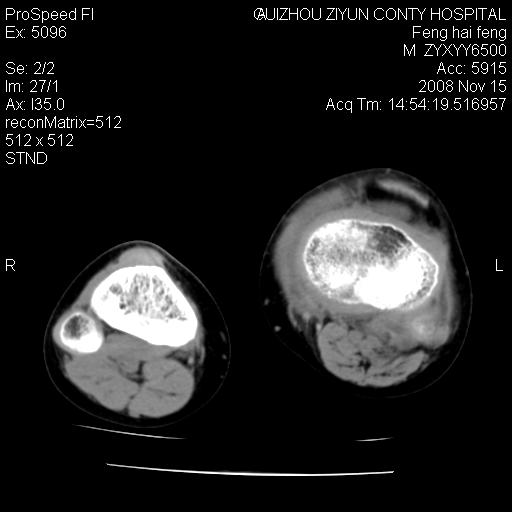

标题: CT16656:M 14Y 左膝关节肿胀一年余。其余病史不详。 [打印本页]

标题: CT16656:M 14Y 左膝关节肿胀一年余。其余病史不详。

考虑左侧髌骨结核;左膝关节滑膜肿胀、增厚,关节囊积液。

左膝滑膜型关节结核可能性大!支持!滑膜型关节结核主要ct表现:关节囊肿胀,积液,关节面见小破坏灶,并见点状死骨!

左膝滑膜型关节结核可能性大!支持!滑膜型关节结核主要ct表现:关节囊肿胀,积液,关节面见小破坏灶,并见点状死骨

好大的左腿!考虑左侧髌骨结核,左膝关节滑膜肿胀、增厚,关节囊积液。

左侧髌骨结核;左膝关节滑膜肿胀、增厚,关节囊积液